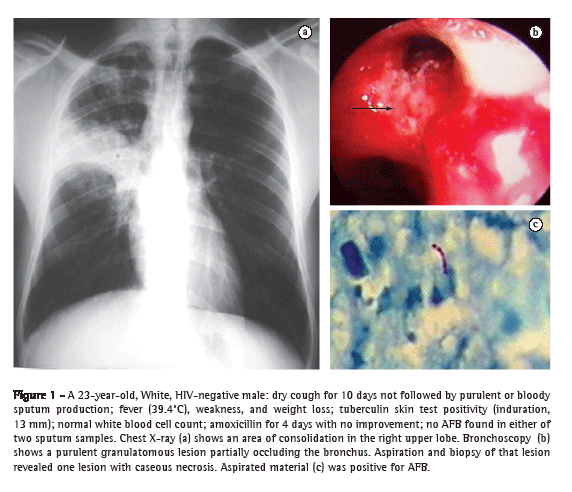

Pulmonary consolidation was found in the upper lobes, primarily on the right, in 40 (67.8%) of the cases, a frequency significantly greater than that observed at other locations (p < 0.001), although the middle lobe was involved in 9 cases (15.3%). Small discrete foci adjacent to the main lesion were seen in most of the patients (Figure 1).

The microbiological confirmation was obtained mainly through sputum smear microscopy, which was positive for AFB in 41 (69.5%) of the 59 patients. Bronchoscopy was performed in 18 patients (30.5%). Bronchial wall lesion was identified and biopsied in 8 (44.4%) of those 18 patients.

The findings were clearly indicative of fistula in 3 (16.7%) and suggestive of fistula (evidence of scarring) in 5 (27.8%). In all eight of those cases, the alterations were identified in large bronchi. In all 18 of the patients submitted to bronchoscopy, the microbiological diagnosis was made through examination of the biopsy fragment or of the BAL fluid (Table 4).